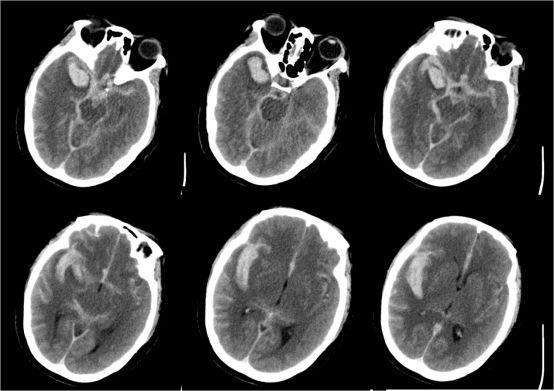

患者术后8小时复查CT

术后复查CTA显示四个动脉瘤夹闭良好,分支血管无狭窄

术后患者,KPS评分100分